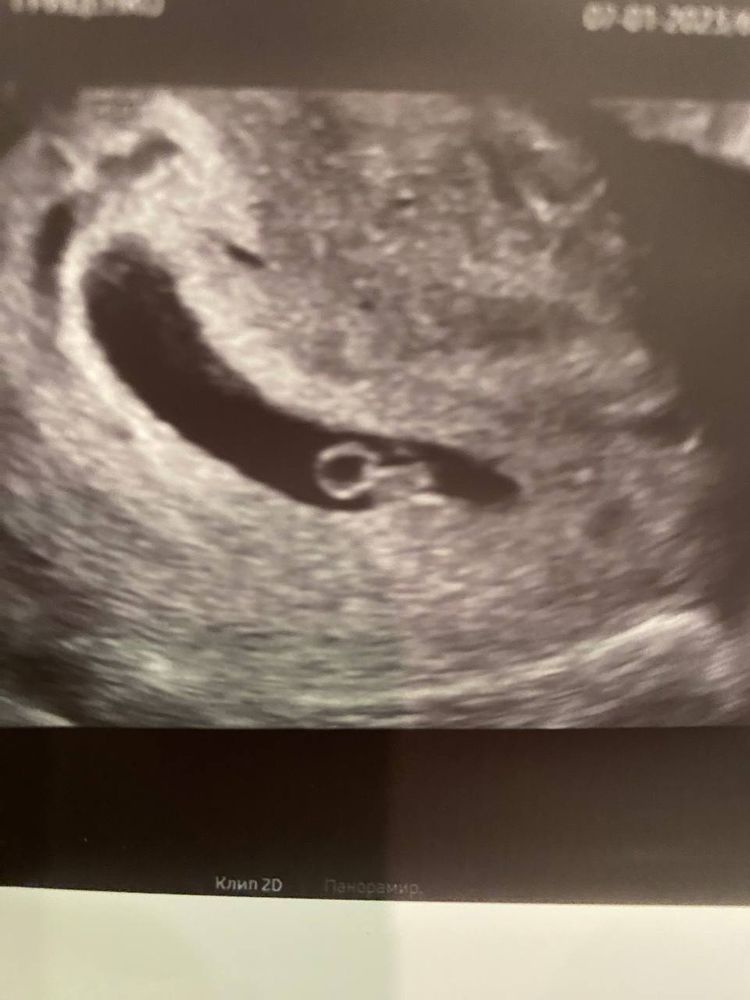

КТР 7.3! что соответствует сроку 6 недель 4 дня

Сердечко бьется 125 уд/мин